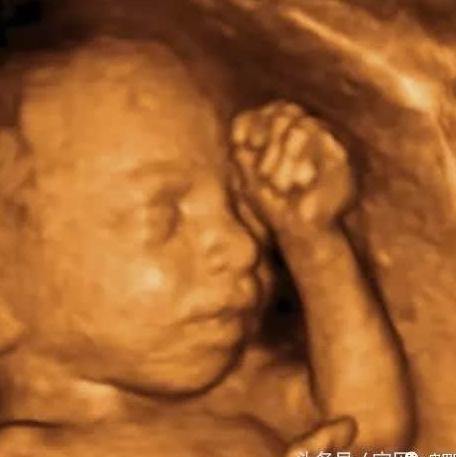

四维超声同其它超声检查相比,可以实时观察人体内部器官的动态运动,也能准确地分辨出胎儿的性别。虽然四维彩超能够看清胎儿的性别,但在检查

说到孕检项目,四维彩超必须得是重磅戏啊!四维彩超是用来排查胎儿畸形的,在怀孕20多周的时候做最准确,由于二胎开放后,现在孕妇特别多,所以做四